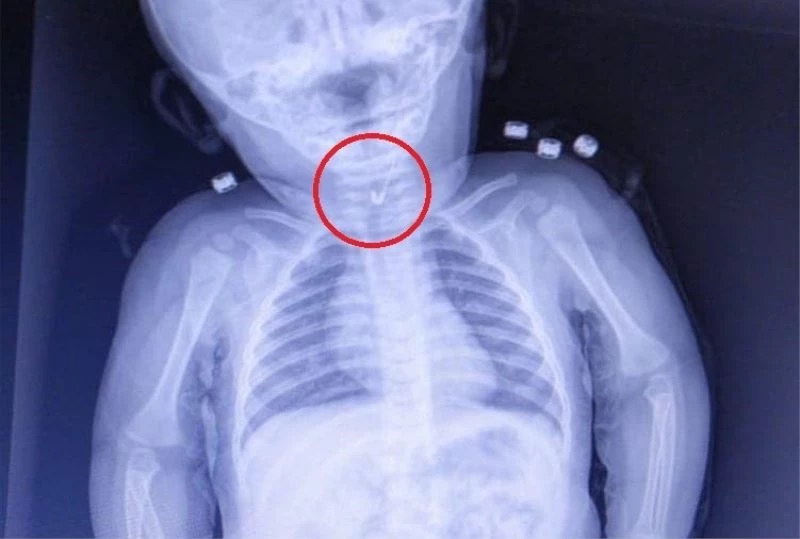

Tekirdağ’da 7 aylık bebeğin yemek borusundan ucu açık çengelli iğne çıktı.

Tekirdağ’da 7 aylık bir bebek, yemek borusuna çengelli iğine kaçması sonucu Tekirdağ Devlet Hastanesine sevk edildi. 7 aylık erkek bebeğin yutup yemek borusuna takılan açık çengelli iğne Tekirdağ Devlet Hastanesi’nde yapılan girişim ile başarıyla alındı. Gastroenterolojik Cerrahi Uzmanı Dr. İhsan Gündüz ile Anestezi Uzmanı Dr. İbrahim Çetin’in yaptığı operasyon sonucu bebek sağlığına kavuştu.